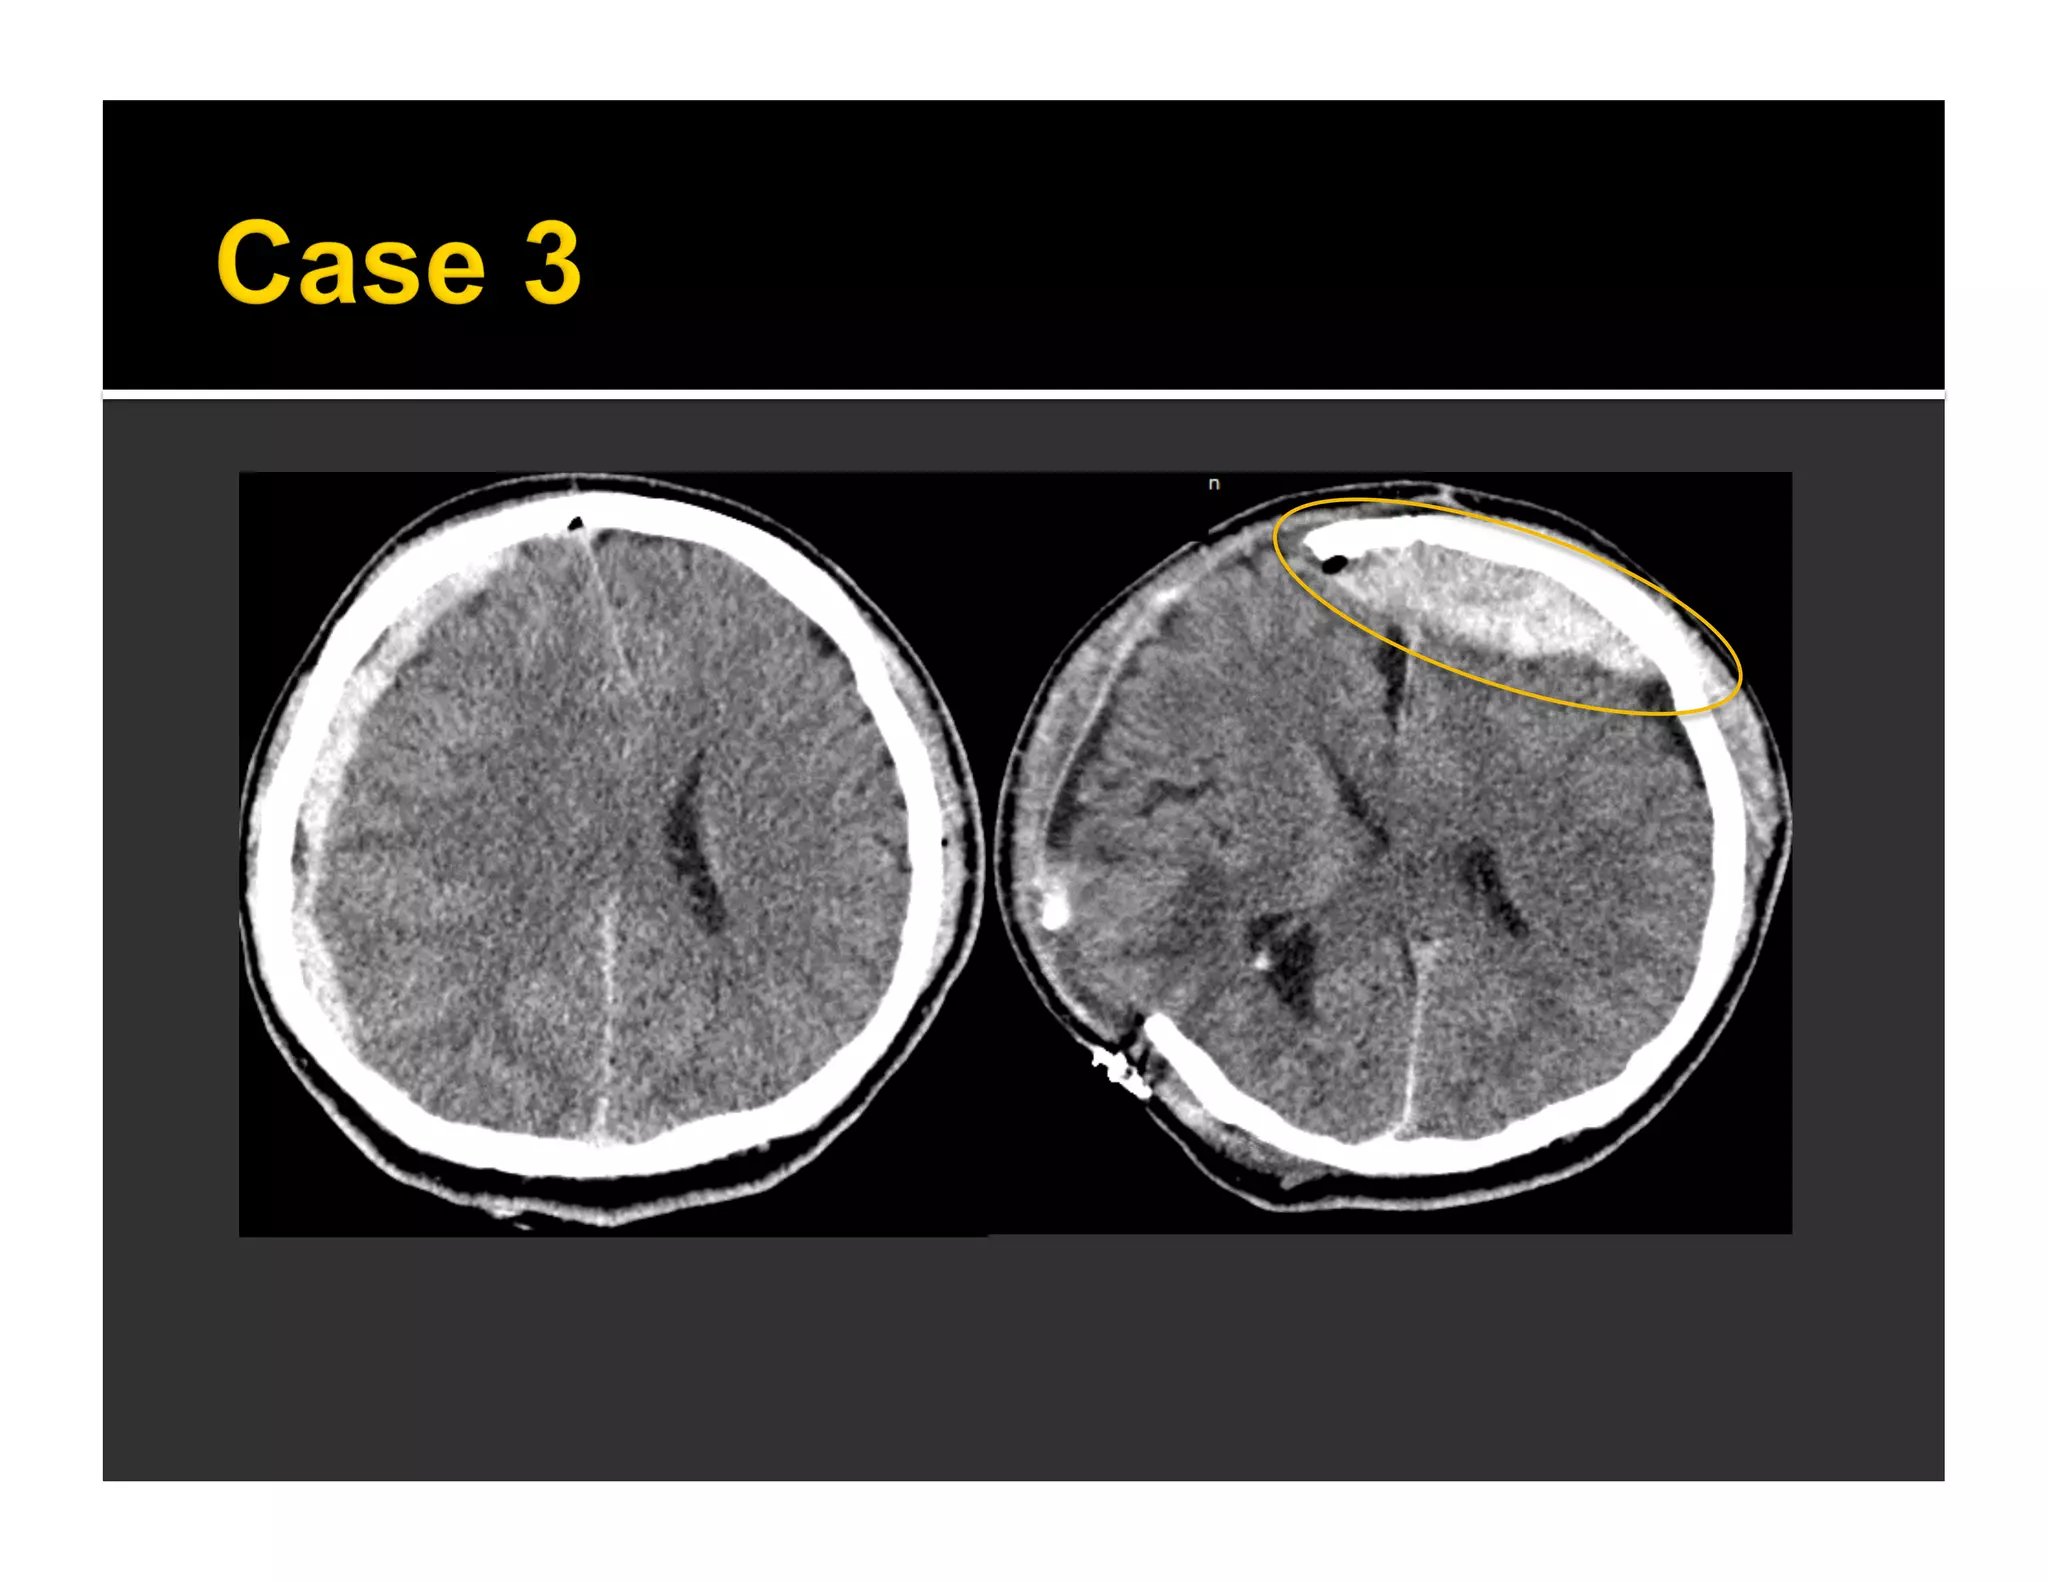

One day later

FLAIR T2W

 Knowing biomechanics of closed TBI

important for detection of lesions and

forensic purpose

 Minimal brain lesions might complete the

mosaic for reconstruction of

biomechanical condition

 Wei SC, et al. AJNR 2010